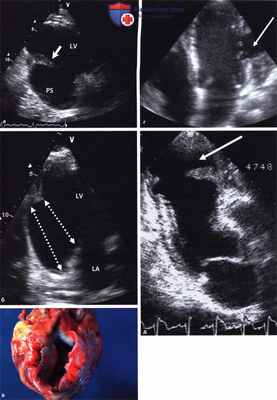

б) Псевдоаневризма. Так обозначается прикрытый склеившимися листками перикарда разрыв свободной стенки левого желудочка, как правило, вследствие инфаркта, но иногда он возникает при травме или даже септическом воспалении. В обширном литературном обзоре, охватившем 290 случаев, псевдоаневризма чаще всего (43%) располагалась в области задней стенки. Критериями отличия от истинной аневризмы являются:

- узкая горловина (в упомянутом исследовании в 82% случаев отношение диаметра горловины аневризмы к ее наибольшему диаметру составило <50%) с более острым углом и более резкими изломами контура, чем у истинной аневризмы, а также

- систолический входящий поток и раннедиастолический выходящий поток крови в области аневризмы, обнаруживаемый в режимах импульсной и цветовой допплерографии.

а - Псевдоаневризма левого желудочка после инфаркта задней стенки. Видна большая полость аневризмы (PS) в области задненижней стенки. Стрелка указывает на заднемедиальную папиллярную мышцу.

б - Пунктирные линии обозначают диаметр «горловины аневризмы» и диаметр в наиболее широкой части; последний больше, чем размер горловины.

в - Секционный препарат со вскрытой псевдоаневризмой. LA - левое предсердие, LV - левый желудочек.

г - Псевдоаневризма боковой стенки (стрелка).

д - Псевдоаневризма верхушки (стрелка).

Но на основании собственного опыта следует сказать, что псевдоаневризма не всегда соответствует описанному «идеальному типу» с узкой горловиной и отчетливыми входящим и выходящим потоками (словно появляется дополнительная камера сердца).

Отрыв головки папиллярной мышцы на фоне инфаркта задней стенки. Парастернальный доступ по длинной оси, слева систола, справа диастола.

Головка папиллярной мышцы (стрелка) движется вместе с передней створкой митрального клапана. У пациента тяжелая митральная недостаточность.

LA - левое предсердие, LV - левый желудочек.